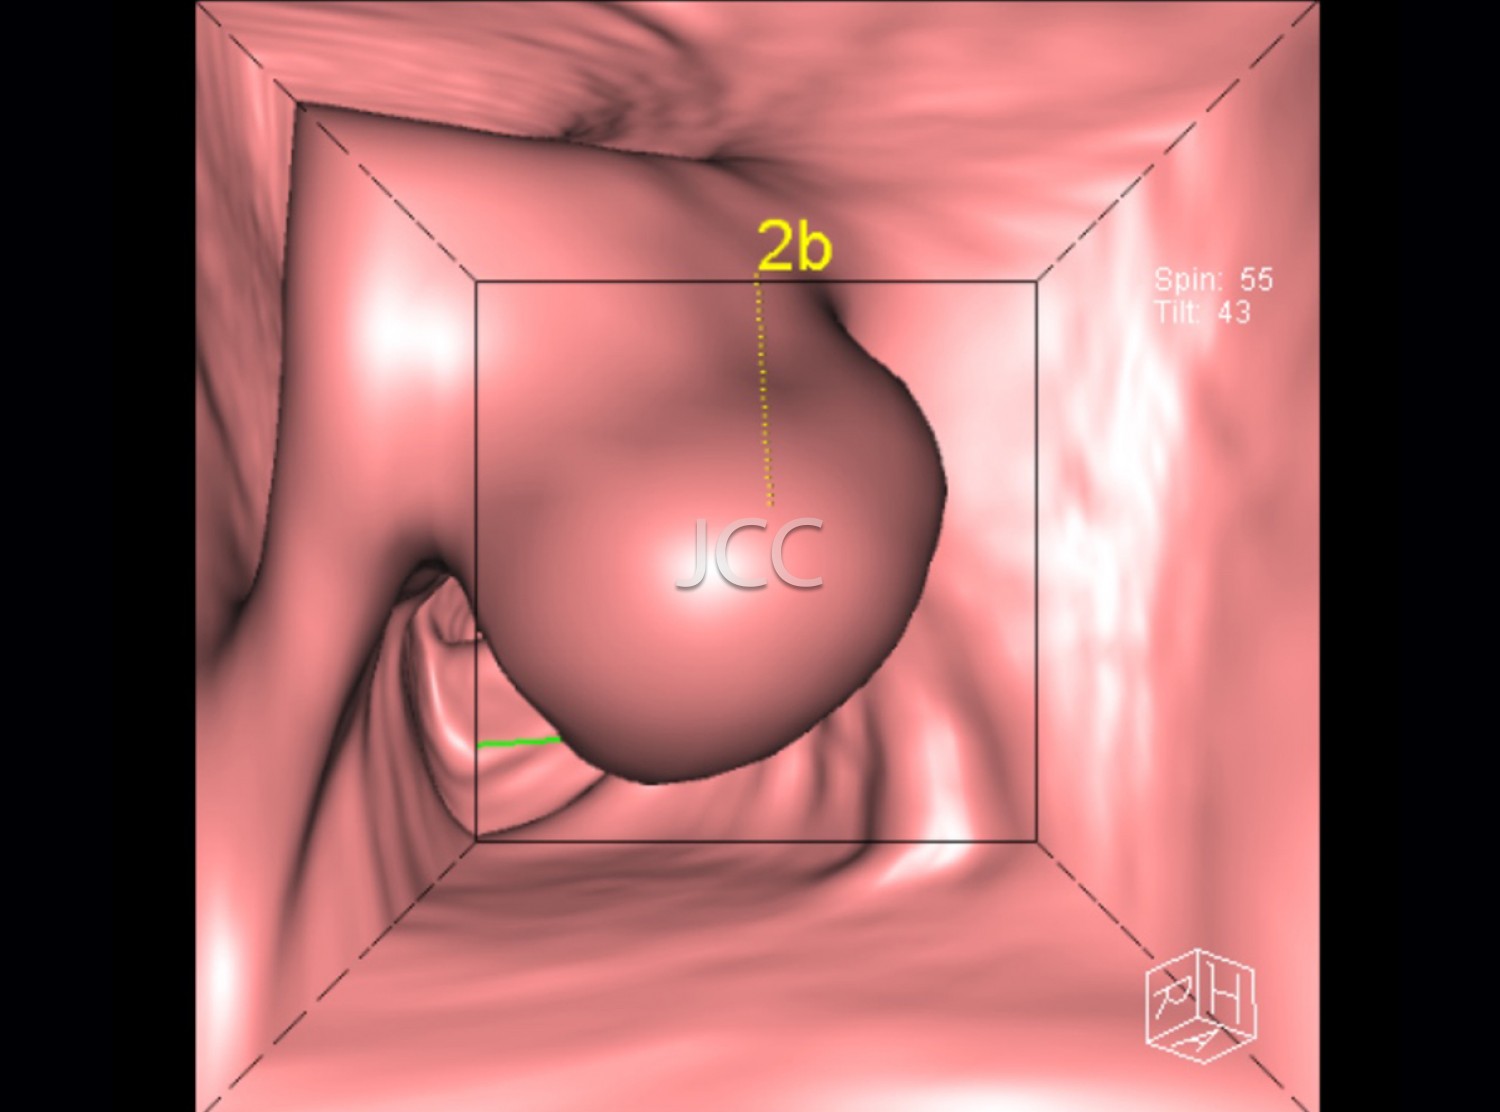

Pela 1ª vez na história da medicina, através da tecnologia multi-detector, com dupla ampola e ressonância magnética de última geração 3 tesla, é possível, de modo não invasivo e capacidade diagnóstica comprovada, efectuar o screening de processos patológicos, para prevenção de doença cardíaca, neoplasias e acidente vascular cerebral – AVC. Salienta-se que com o nosso equipamento de TAC dual source - 256 cortes -  a dose de radiação é  muito baixa (cerca de 10 vezes inferior à dose dos equipamenos de TAC de 64 cortes).  Os dados obtidos nestes equipamentos de ultima geração são tratados em estações de trabalho de alto nível, que utilizando sistemas CAD e de visualização tridimensional, resulta em informação detalhada e muito rigorosa.

O conjunto destes exames com este tipo de equipamento constitui a modalidade de escolha para o estudo imagiológico do corpo humano, através de angiografia não invasiva do coração, do cérebro e dos vasos do pescoço, colonoscopia virtual por TAC assim como a avaliação dos restantes orgãos e estruturas ósseas do tórax, do abdomen e da pélvis, o estudo da próstata no caso do homem e da mama no caso da mulher.

CHECK-UP CARDIO-TORÁCICO

• Angio TC das Coronárias